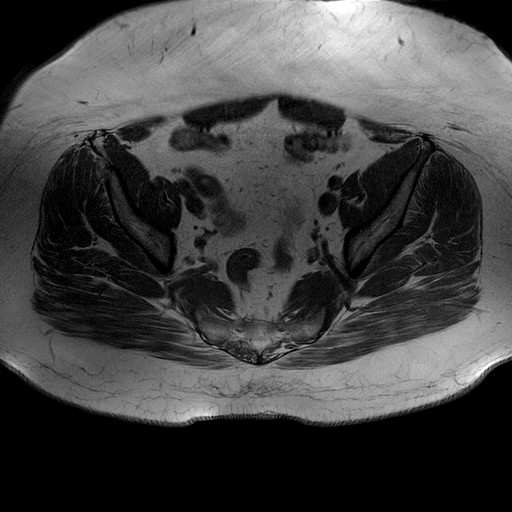

Esami: RMN BACINO

T1W_TSE

Evidenti e simmetriche alterazioni osteofitosiche in regione coxo femorale con riduzione delle rime articolari. Degenerazione completa del cercine glenoideo. Non attuali segni di versamento articolare. Non segni di edema osseo che escludono attuale algodistrofia od osteonecrosi. Lieve e simmetrica riduzione del trofismo della muscolatura glutea.